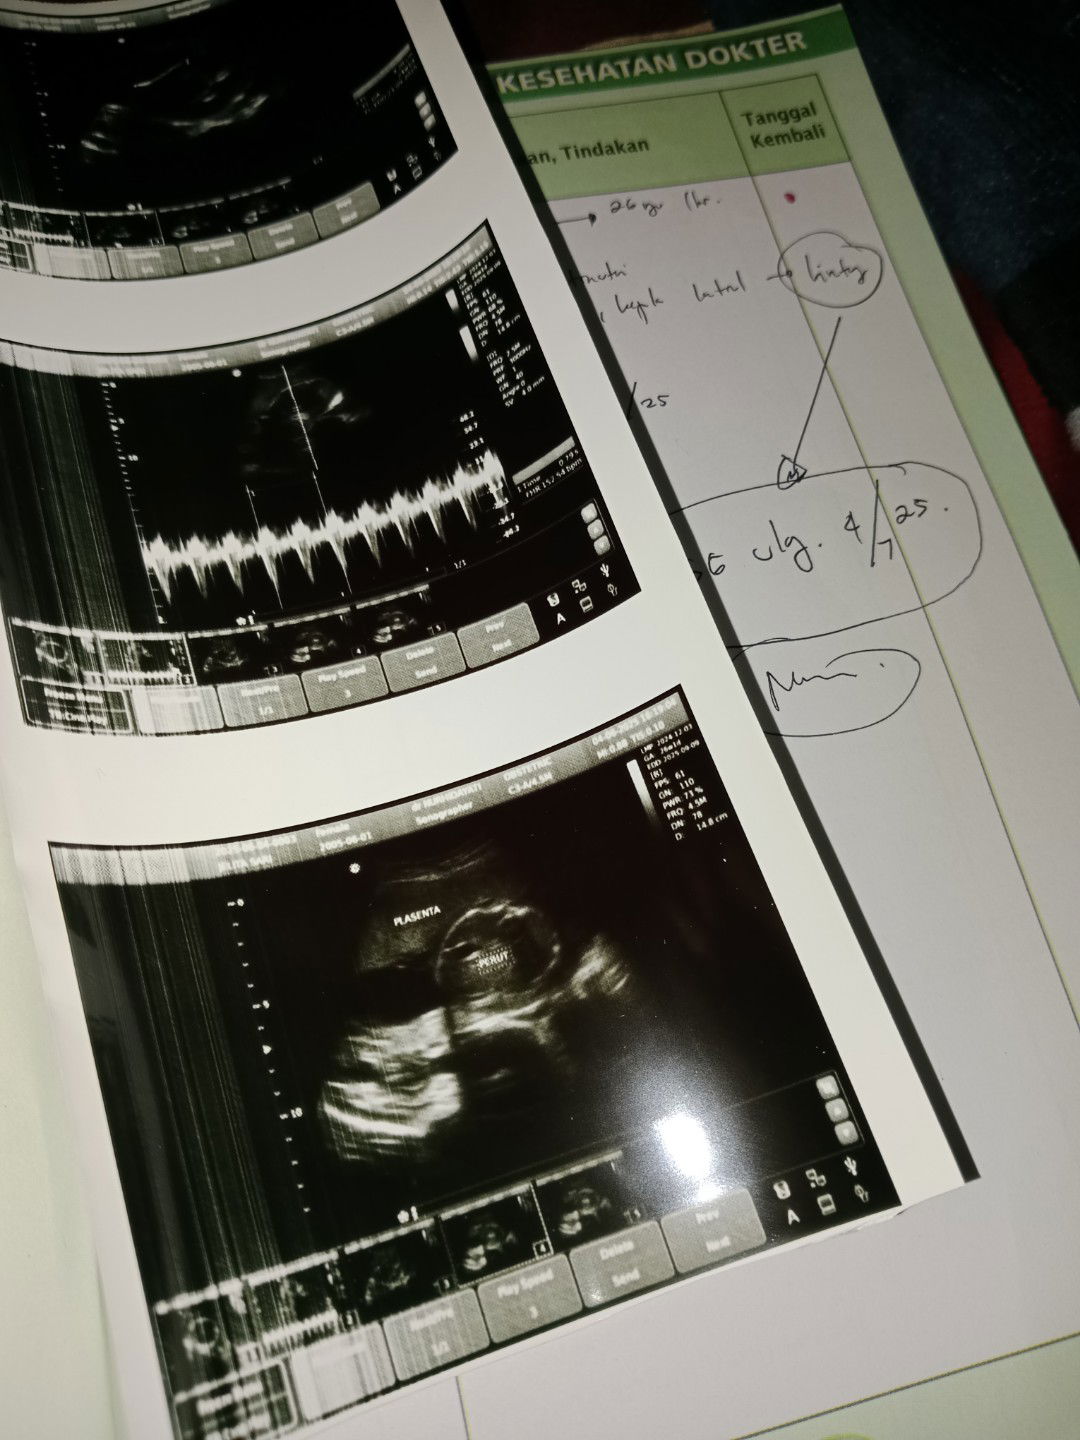

USG untuk mendeteksi kelainan down sindrom

Usg diusia kandungan berapa week jika ingin mendeteksi kelainan dini? #firstmom #firsttimemom #betulbetultanya

Maks 13 week kak, aku jg minggu ini 13 week disuruh usg buat screening down syndrom

12 minggu